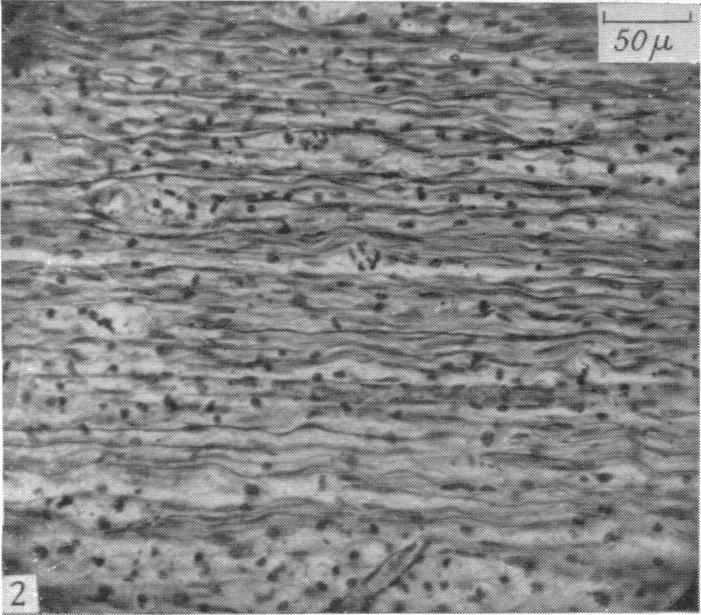

The degeneration and re-innervation of grafted nerves.

J Anat. 1942 Jan;76(Pt 2):143-166.7.